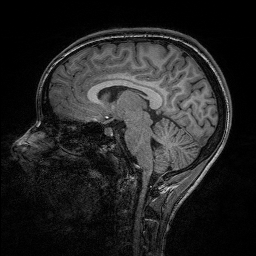

Improving image reconstruction from a sparse set of known pixels was the main motivation behind our work. Therefore, we applied it to two well-known natural images, lena and peppers, as well as to a medical image, a slice of a weighted brain MR scan (t1slice). For lena, we kept a random subset of only of the pixels. Due to the lower resolution of the peppers and t1slice images, we kept and , respectively.

Results for lena are shown in Figure 2, for peppers in Figure 3, and for t1slice in Figure 4. A quantitative evaluation in terms of MSE and AAE is presented in Table 4.1. In terms of the numerical results, our proposed method produced a more accurate reconstruction than any of the competing approaches. Visually, there is a clear difference between second-order (EED) and fourth-order approaches (Li1, Li2, FOEED). Especially, we found that the shapes of edges were reconstructed more accurately. For example, we noticed this around the shoulder and hat in the lena image (Figure 2). Similarly, the white and grey matter boundaries were better separated in the t1slice (Figure 4).